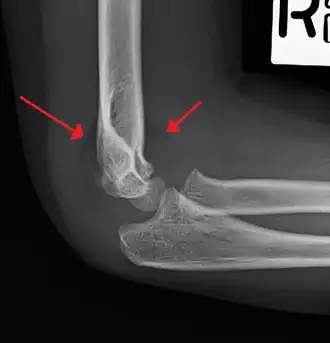

On lateral view of the elbow, there are five radiological features should be looked for: tear drop sign, anterior humeral line, coronoid line, fish-tail sign, and fat pad sign/sail sign (anterior and posterior).[3][8]

Tear drop sign - Tear drop sign is seen on a normal radiograph, but is disturbed in supracondylar fracture.[8]

Anterior humeral line - It is a line drawn down along the front of the humerus on the lateral view and it should pass through the middle third of the capitulum of the humerus.[9] If it passes through the anterior third of the capitulum, it indicates the posterior displacement of distal fragment.[8]

Fat pad sign/sail sign - A non-displaced fracture can be difficult to identify and a fracture line may not be visible on the X-rays. However, the presence of a joint effusion is helpful in identifying a non-displaced fracture. Bleeding from the fracture expands the joint capsule and is visualized on the lateral view as a darker area anteriorly and posteriorly, and is known as the sail sign.[8]

Coronoid line - A line drawn along the anterior border of the coronoid process of the ulna should touch the anterior part of the lateral condyle of the humerus. If lateral condyle appears posterior to this line, it indicates the posterior displacement of lateral condyle.[8]

Fish-tail sign - The distal fragment is rotated away from the proximal fragment, thus the sharp ends of the proximal fragment looks like a shape of a fish-tail.[8]

Anterior and posterior sail sign in a child who has a subtle supracondylar fracture -